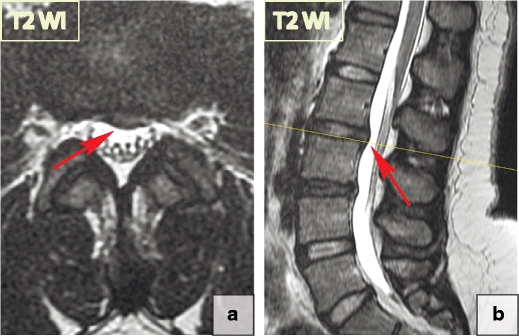

Intraosseous Pneumatocyst Radsource